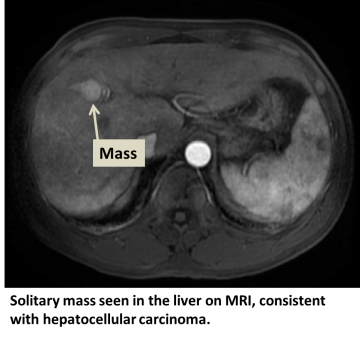

Hepatocellular carcinoma (HCC) is the most common type of primary liver cancer. Primary liver cancer refers to cancer that originates in the liver rather than cancers from other organs that metastasize to the liver (see metastatic liver cancer). HCC can start as a single tumor or as several tumor nodules across the liver.

In addition to a physical examination, laboratory tests and imaging studies may be needed. These tests may also be necessary at regular intervals to detect early cancer if certain risk factors are present. Our physicians may enroll you into such a screening or surveillance program. The tests may include:

- MRI